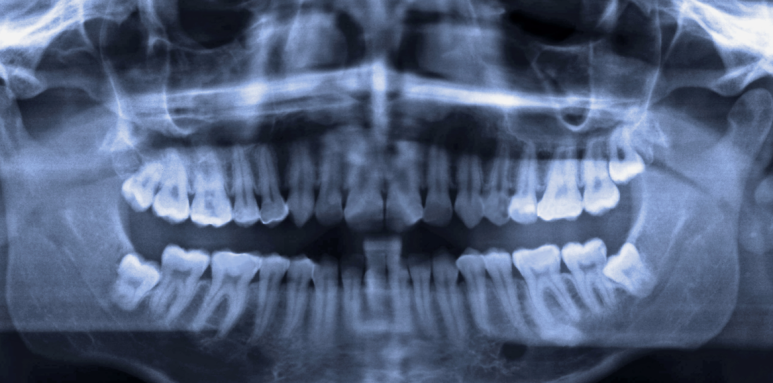

제가 CT를 찍어보면 뼈가 충분한 분도 계시고, 거의 종잇장처럼 얇아진 분도 계세요.

사실 3D CT 한 장이면 뼈이식이 필요한지, 어떤 브랜드가 적합한지 바로 확인할 수 있습니다.

3D CT 한 장이면 지금 뼈 상태가 어떤지, 뼈이식 없이 가능한지 바로 확인해드릴 수 있어요.

내 뼈 상태에서 뼈이식이 정말 필요한 건지, 어떤 브랜드가 맞는 건지

— 이건 CT 한 장이면 바로 볼 수 있죠. 나온 결과는 제가 직접 확인하고 솔직하게 말씀드립니다.